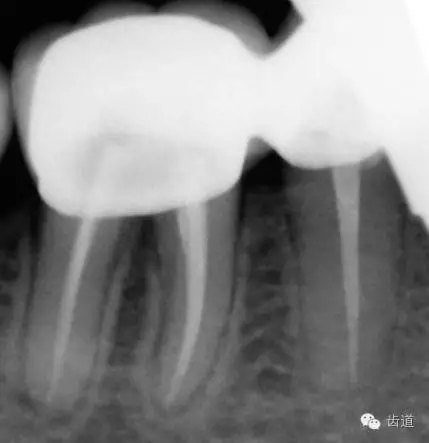

45,46去除原充填物和齲壞,揭全髓室頂,46探及近頰近舌遠(yuǎn)中三根管,45單根管,超聲輔助清理髓腔及根管,去除根管內(nèi)充填物,根管下段細(xì)小堵塞欠通暢,8號(hào)/10號(hào)C銼疏通根管,pathfile+protaper鎳鈦根管預(yù)備,熱牙膠根管充填。

5、34冠修復(fù),45,46聯(lián)冠修復(fù)(2013年10月)

6、45,46,47牙片